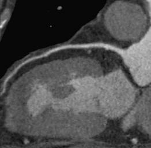

Основным направлением в использовании новой

технологии, безусловно, является кардиология, или, если быть более точным,

исследование коронарных артерий сердца. Многочисленные исследования последнего

десятилетия показали, что МСКТ сердца с использованием полюсного внутривенного

контрастирования позволяет всесторонне изучить внутренний просвет и состояние

стенок коронарных артерий. Наибольшее клиническое значение имеет высокий

отрицательный предсказательный уровень в отношении стеноза коронарных артерий.

Это означает, что если по данным МСКТ с полюсным контрастированием просвет

коронарных артерий не изменен, обычно нет необходимости выполнять прямую

(катетеризационную) коронарографию. Это относится и к планированию более

сложных интервенционных лечебных процедур, таким как баллонная дилятация и

стентирование коронарных артерий, а также аортокоронарного шунтирования. Однако